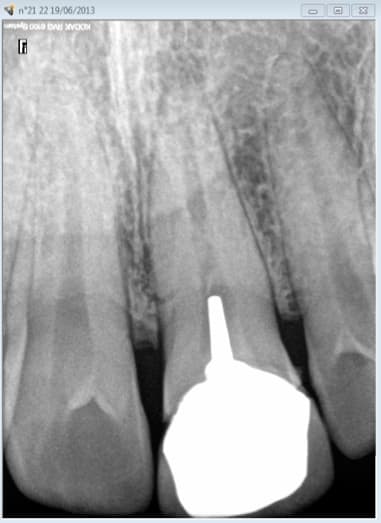

chicot29

celle là est pas mal mais en sens inverse.De la pate avant mais plus après pose de l'ic coiffe dans le palatin.

le patient s'en est aperçu 5 ans après suite à un signe d'appel.

Ce patient c'est moi. -)

Capteur VS plaque il n'y a pas photo. -)